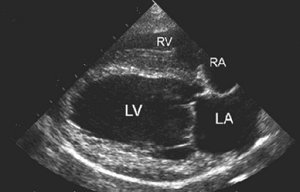

As discussed in more detail below,

mitral

regurgitation (MR) is blood moving backwards through the

mitral valve from

the left ventricle to the left atrium. This backflow usually makes a

soft sound, called a mumur, that can be heard with a stethoscope

(auscultation). In some milder cases, the sound of the backflow cannot

be heard, but it can be observed during echocardiograph scans.

(In the image at right, the red spurt of blood is shooting upward and backward, from the left ventricle, through the not-fully-closed mitral valve, back into the left atrium.)